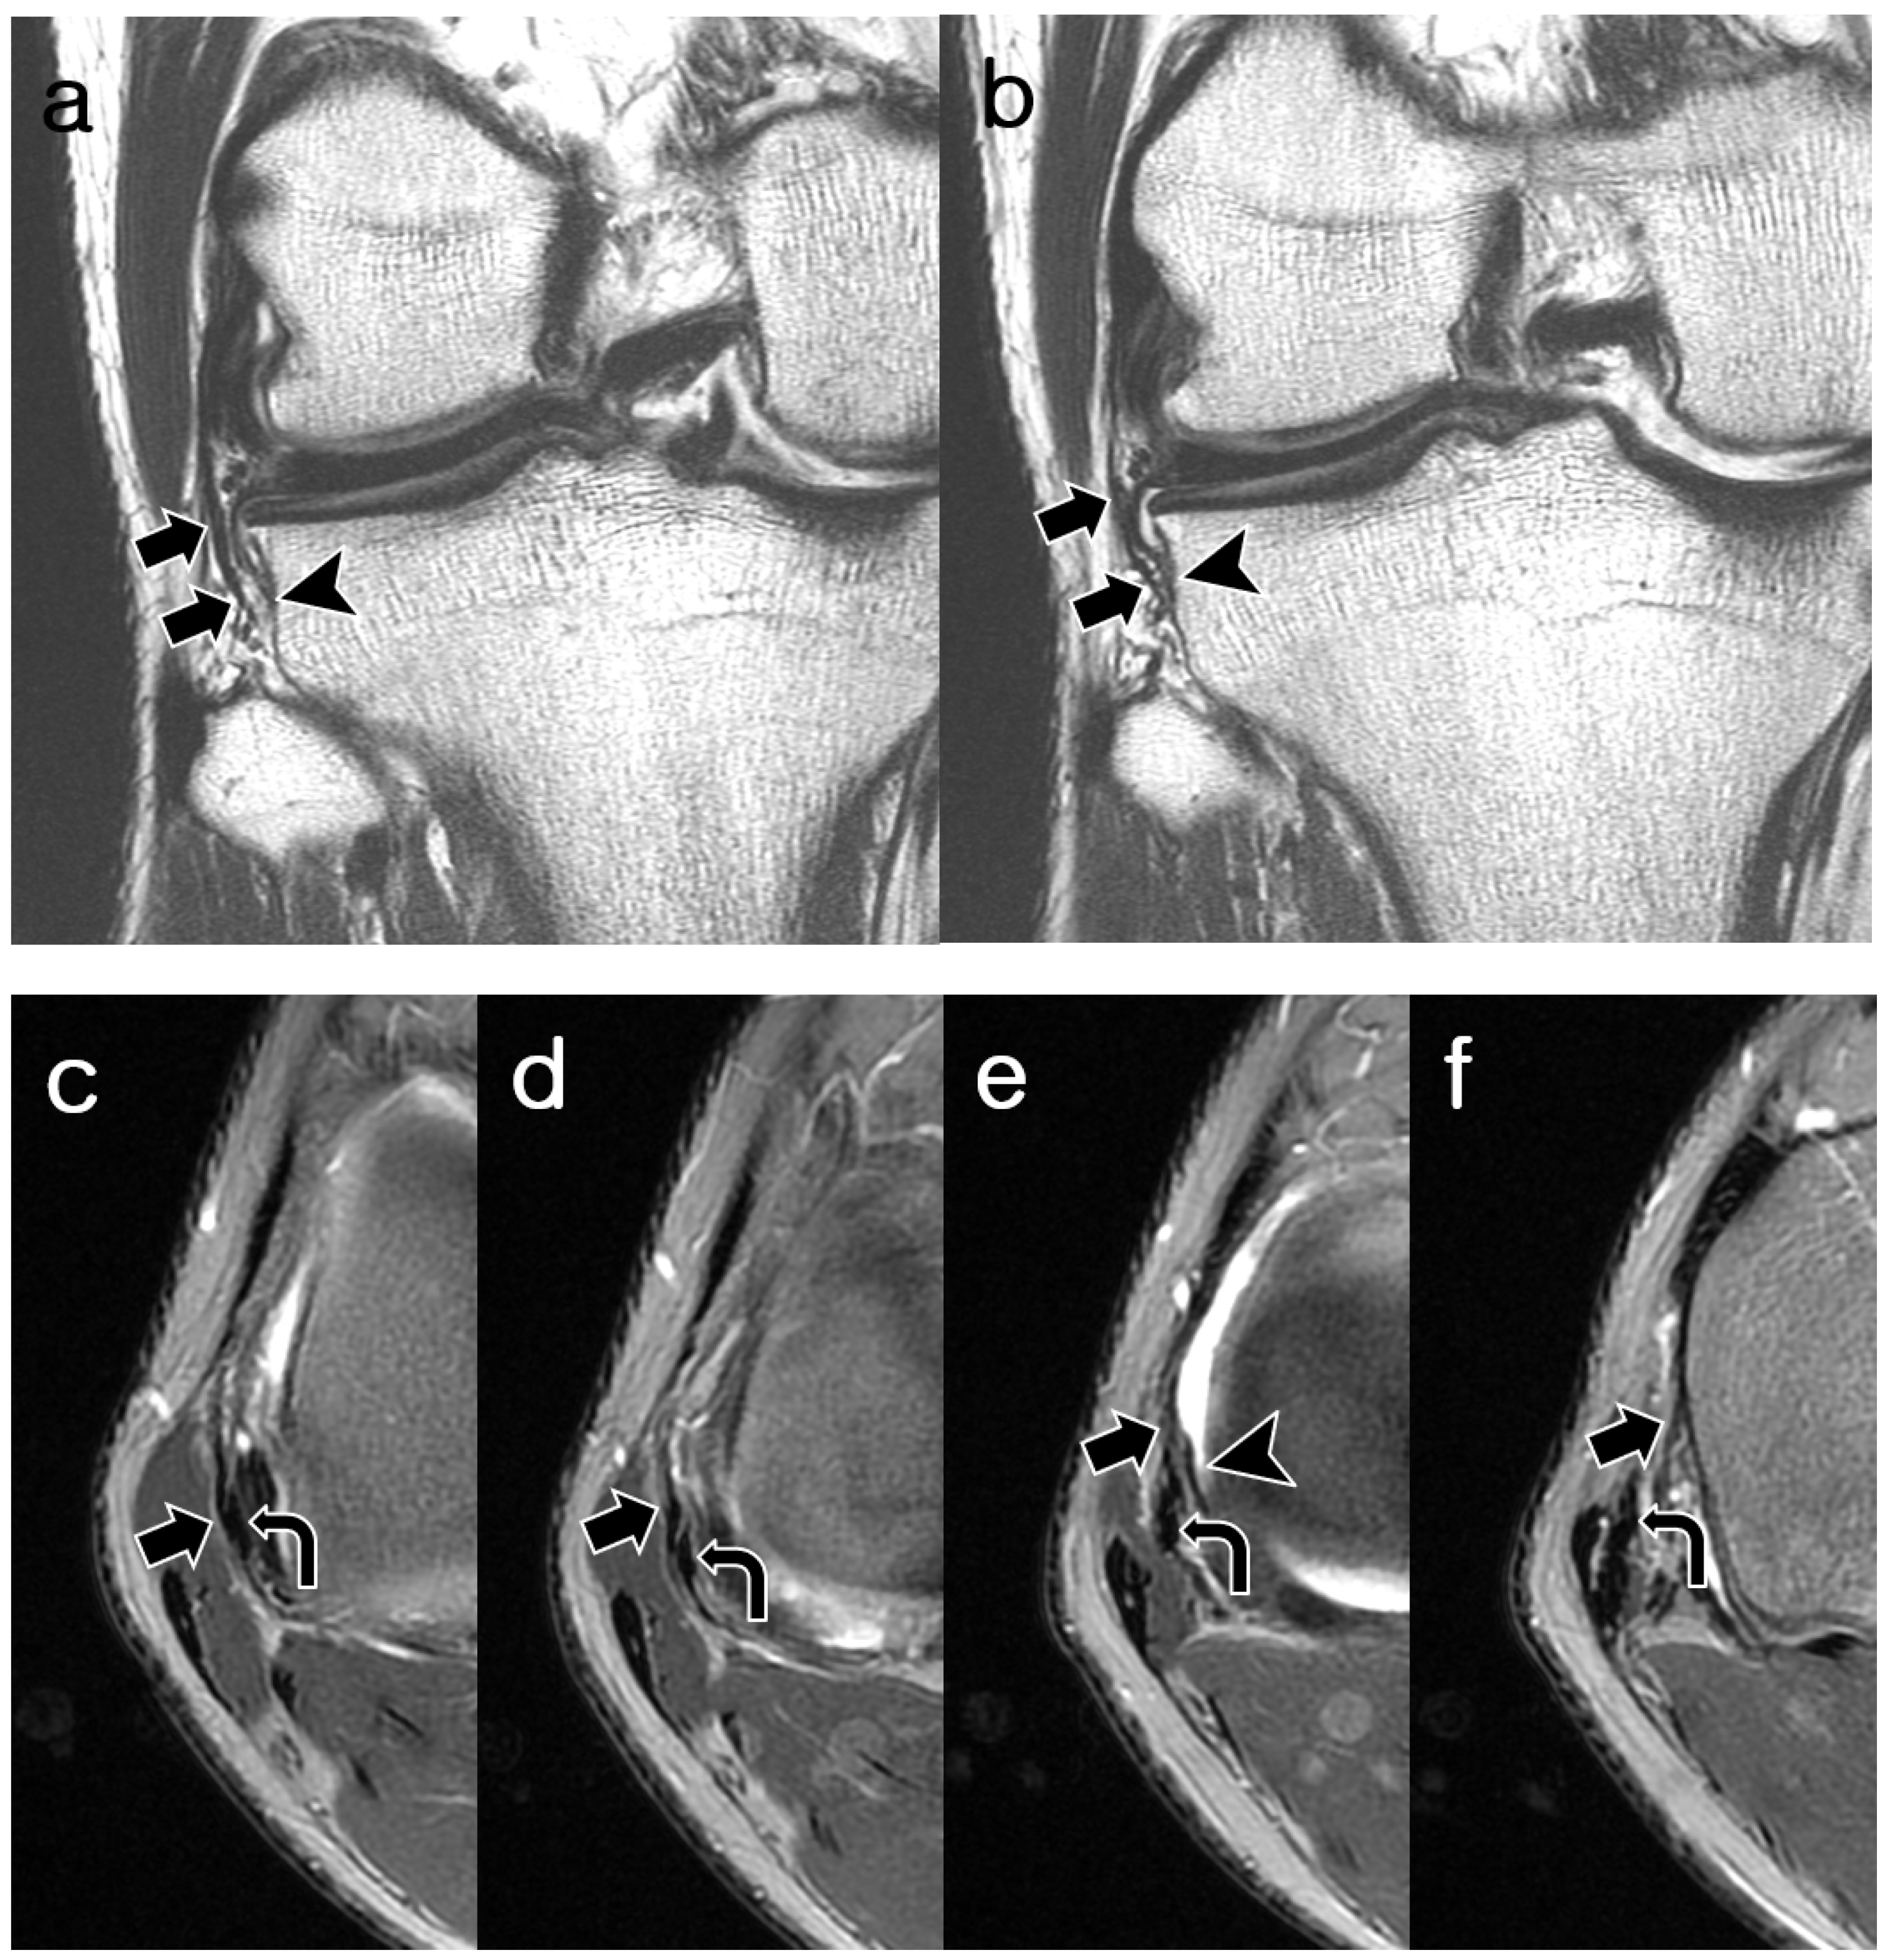

3.2. ALL Visibility

3.3. ALL Morphology